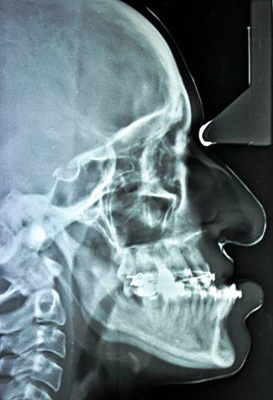

MAXILLARY LEFORT I ADVANCEMENT

BILATERAL SAGITAL SPLIT OSTEOTOMY SETBACK |

| Pre-Op Profile |